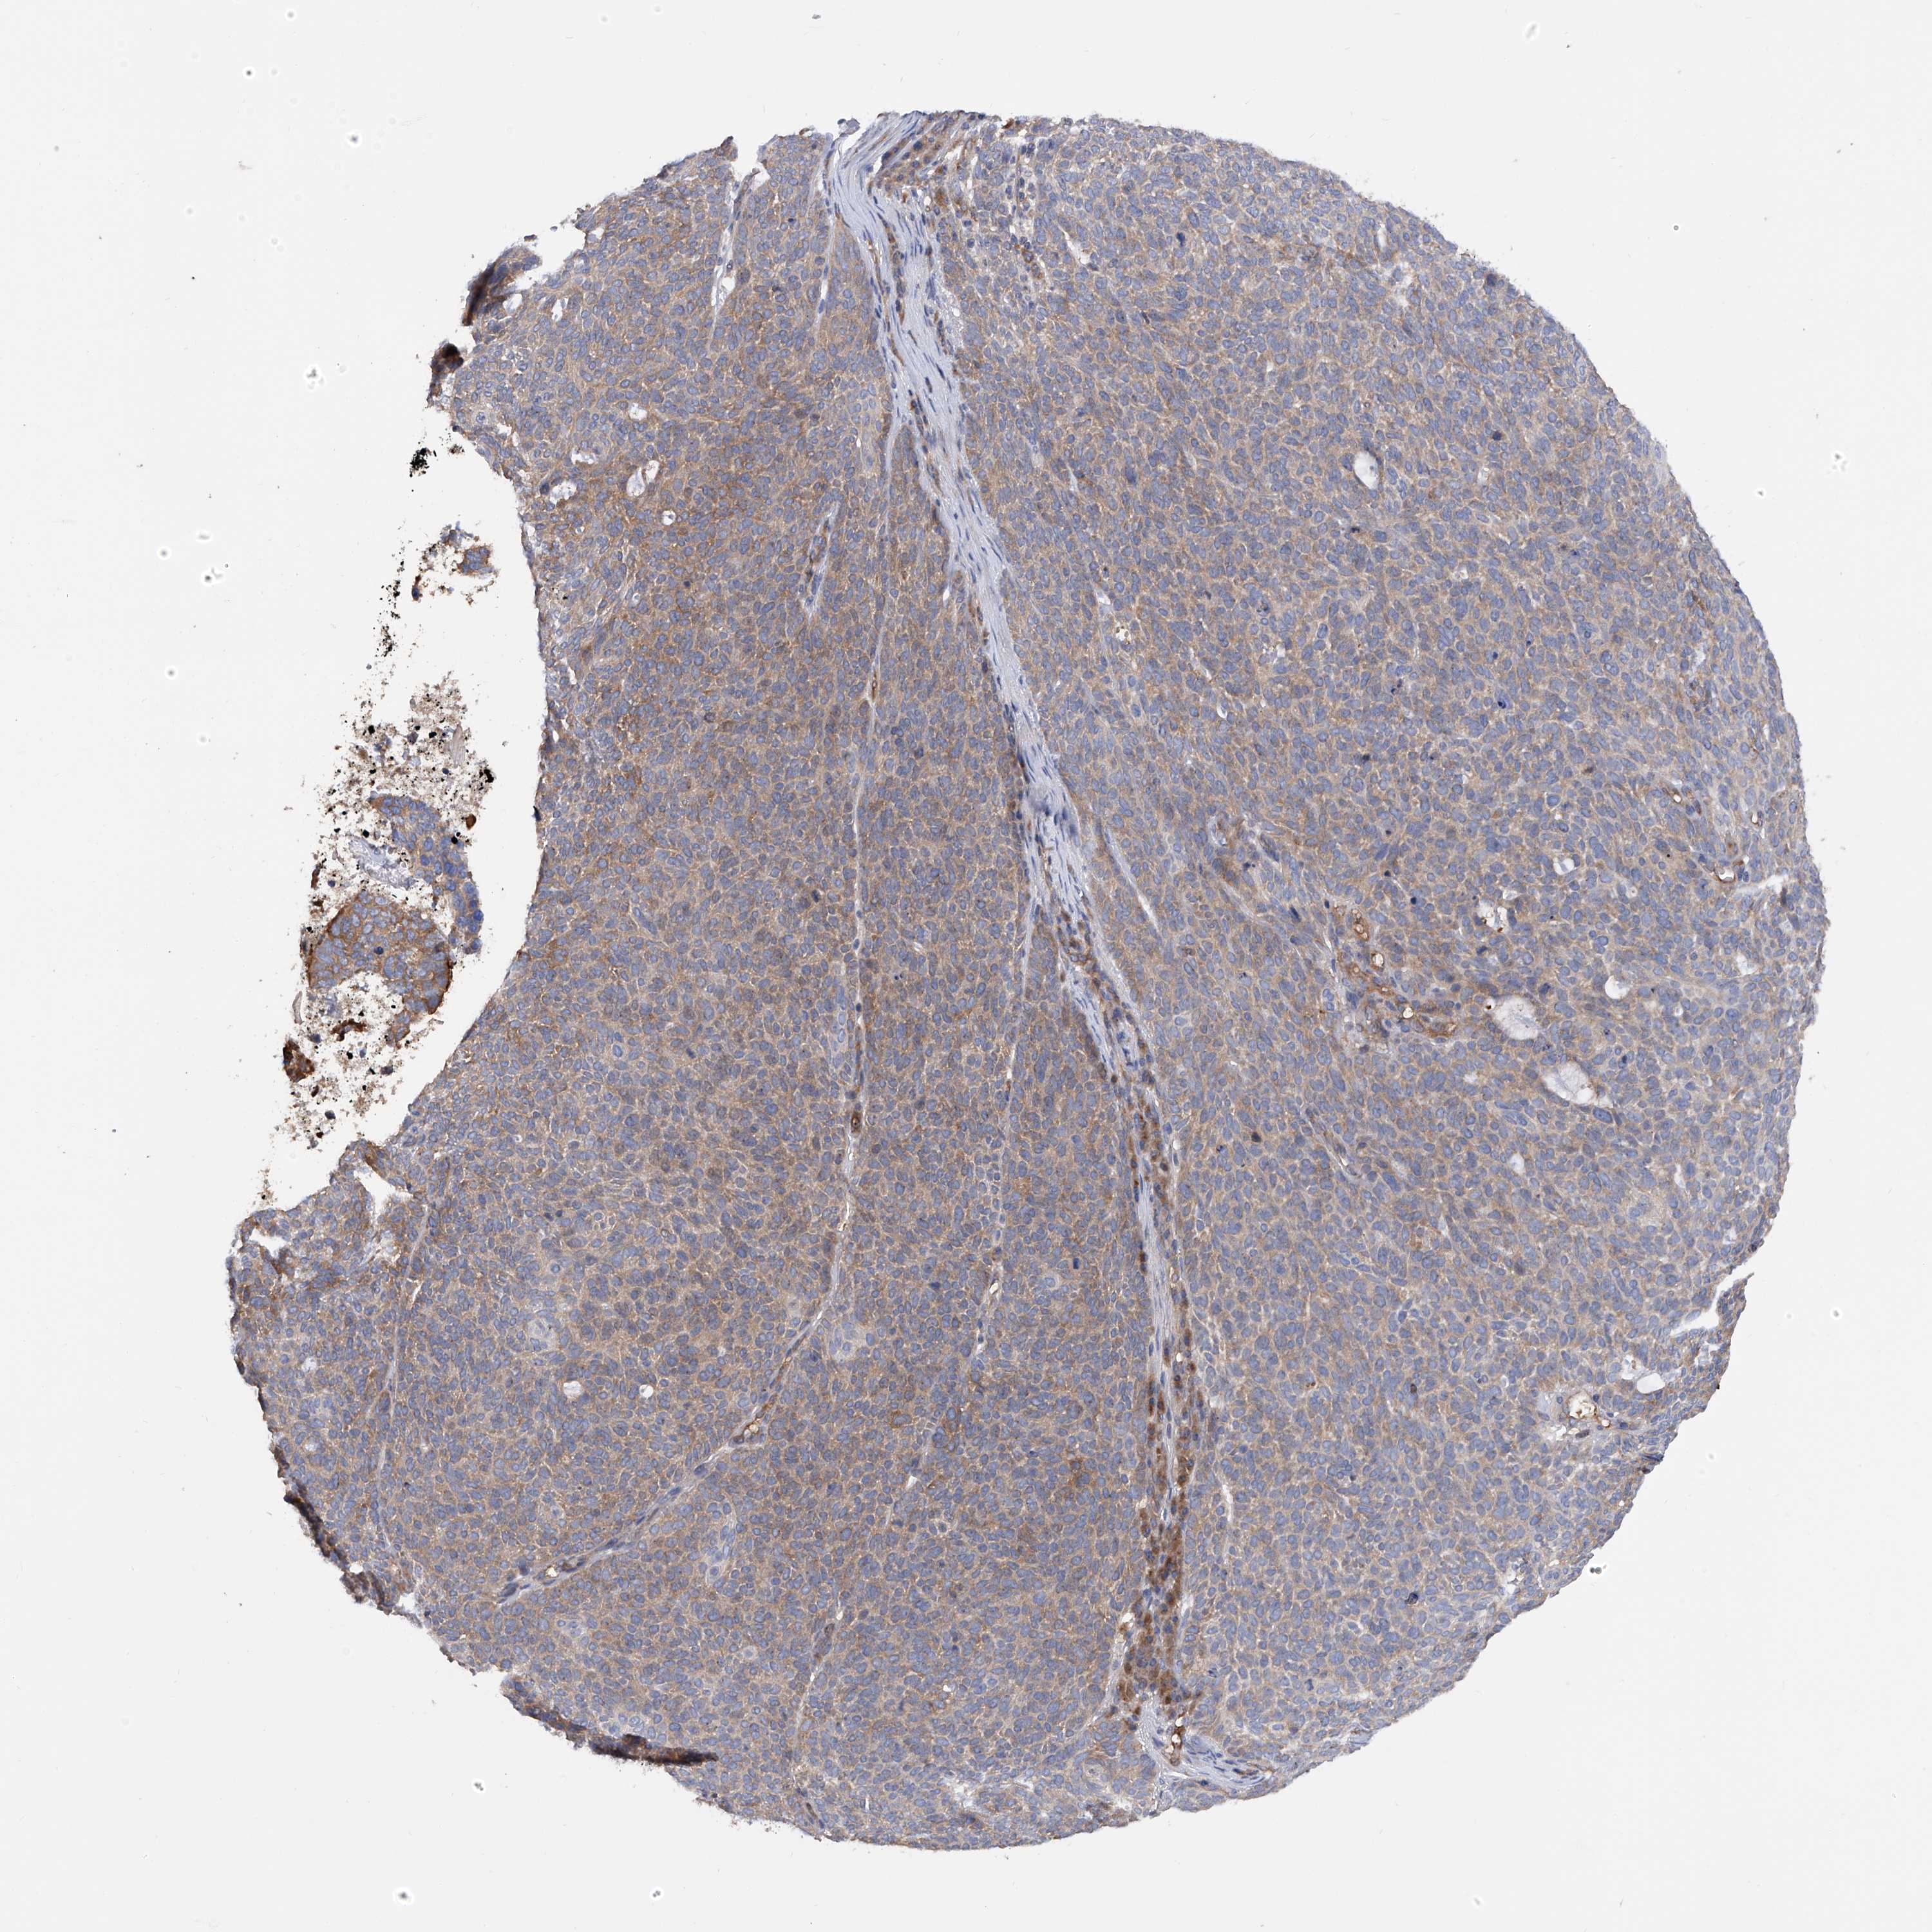

Basal cell and squamous cell cancer

SKIN CANCER - Protein expressioni

A mouse-over function shows sample information and annotation data. Click on an image to view it in a full screen mode. Samples can be filtered based on level of antibody staining by selecting one or several of the following categories: high, medium, low and not detected. The assay and annotation is described here.

Each image is clickable and will lead to virtual microscopy that enables deeper exploration of all samples and also displays staining intensity scores, fraction scores and subcellular localization as well as patient and tissue information for each sample.

Antibody HPA030145

Staining

Medium

Moderate

75%-25%

Location

Cytoplasmic/membranous

Squamous cell carcinoma, NOS